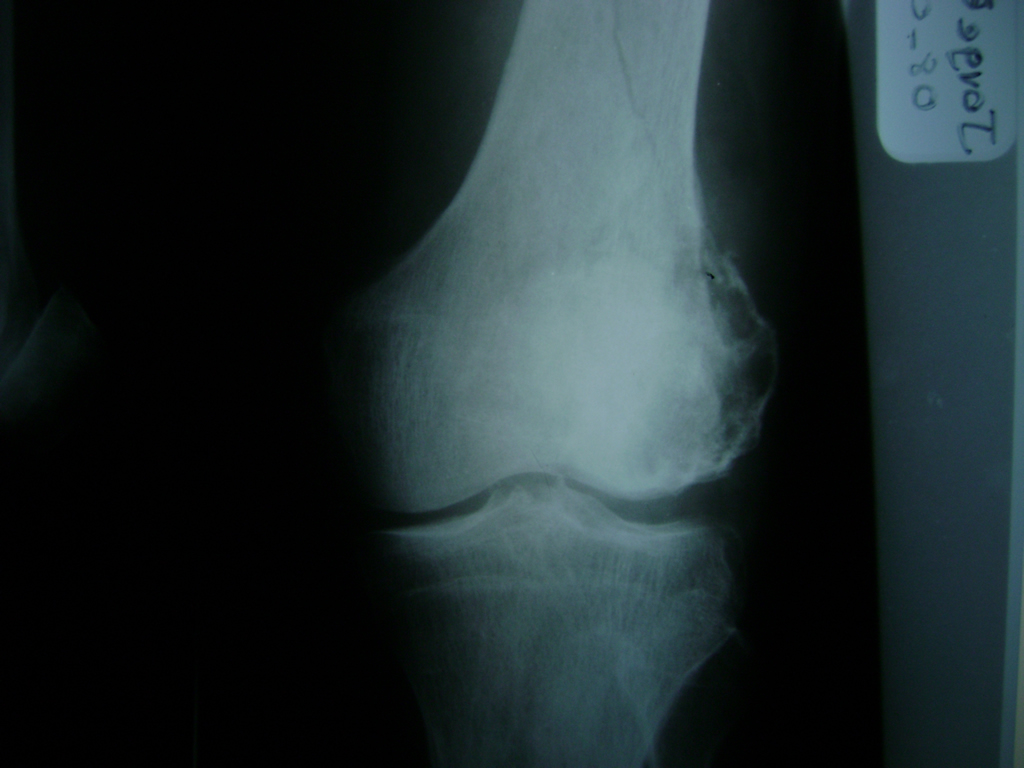

Cirugía de Fémur - Rodilla

La artroscopia de rodilla es un cirugía en el cual la estructura interna de la articulación es examinada ya sea para realizar un diagnostico o para realizar un tratamiento, este procedimiento se realiza utilizando un instrumento parecido a un pequeño tubo llamado artroscopio.